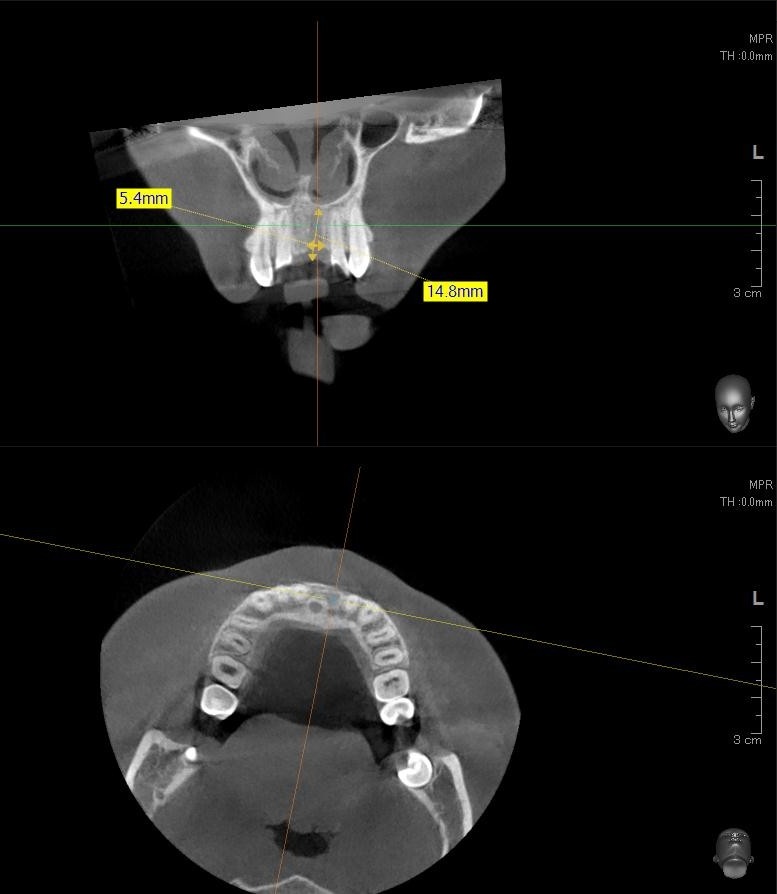

今回の患者様はインプラント植立を希望され、左上1番目の植立が決まりました。

ドリルの先端を細い物から徐々に大きい物に変えながら、植立するインプラント体のネジの部分を除いた胴の部分の太さに合わせた大きさの穴を開けていきます。

開けた穴に、専用道具を使ってネジを締めるように長さ2センチ程のインプラントを骨に埋め込んでいきます。